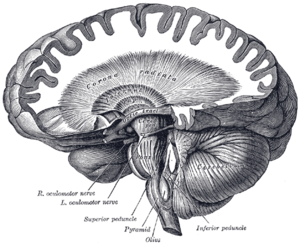

The corticospinal tract constitutes a large part of the internal capsule, carrying motor information from the primary motor cortex to the lower motor neurons in the spinal cord. Above the basal nuclei the corticospinal tract is a part of the corona radiata, below the basal nuclei the tract is called crus cerebri (a part of the cerebral peduncle) and below the pons it is referred to as the corticospinal tract.

Superficial dissection of brain-stem. Ventral view. Coronal section of brain immediately in front of pons.

Coronal section of brain immediately in front of pons. Dissection showing the course of the cerebrospinal fibers.